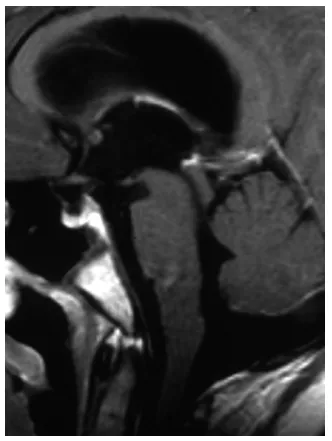

我们直接转入施罗德教授所在的医疗机构,计划次日进行内镜下第三脑室造瘘术以缓解脑积水,同时实施肿瘤活检术明确病变性质。然而命运开了残酷的玩笑——入院当天昭昭突然陷入昏迷状态。急诊MRI显示带蒂肿瘤完全坠入导水管(图2),造成完全性梗阻。医生严肃表示:“必须立即手术。”

图2. 昏迷后急诊矢状位T2加权MRI可见带蒂肿瘤深部移位至导水管内,形成完全性梗阻。